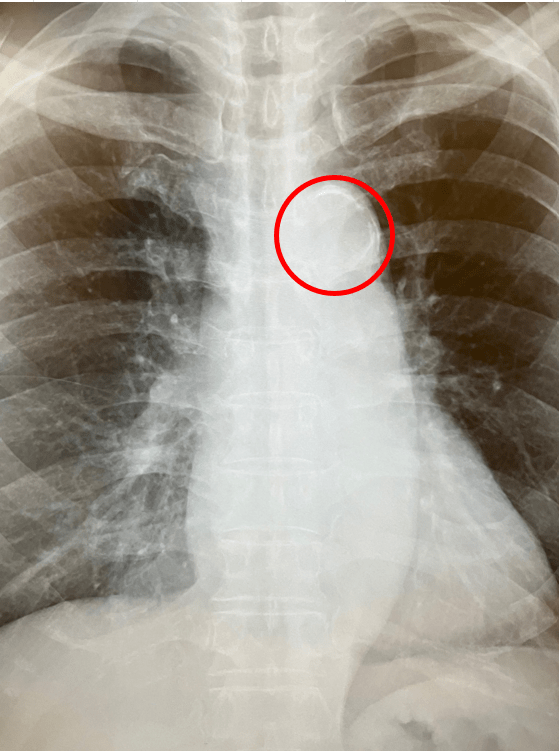

胸部レントゲン検査の画像。大動脈の壁にカルシウムが沈着し、石灰化していることがわかる(赤丸部分) 資料提供=東丸貴信医師

このように、大動脈に石灰化があれば全身の動脈硬化が進んでいるといえます。実際に大動脈石灰化があると、心疾患や脳卒中のリスクが数倍増加することが複数報告されています。

ですので石灰化が見られたら放置せずに、首の血管(頸動脈)や心臓の血管(冠動脈)など全身の血管をチェックしたほうがいいでしょう。